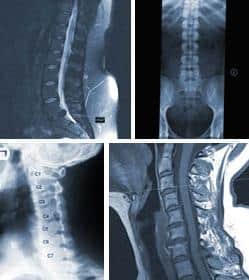

Common tests for a patient with low back and lower extremity pain may undergo include lumbar spine x-rays (films), CT scans (computed axial tomography scans), MRI scans (magnetic resonance imaging), myelograms, post myelographic CT scans, EMG/NCV (electromyogram/nerve conduction velocity) studies, discograms, and bone density tests.